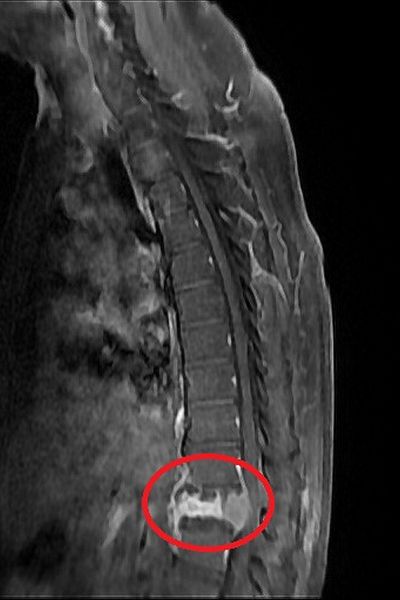

60歲的邱先生過往沒有慢性病史也沒有特別定期健檢,一個月前突然出現雙腳無力的狀況,並且越來越嚴重,來院前無法站立行走,輾轉來到台北慈濟醫院神經外科洪立偉醫師門診尋求協助。透過X光、核磁共振檢查,發現邱先生胸椎第12節有塌陷情形,且已經壓迫神經管,影像懷疑為腫瘤骨轉移導致的非單純骨質疏鬆之壓迫性骨折,進一步抽血檢查更顯示腫瘤標記數值增高。經解釋後,洪立偉醫師遂執行「減壓及微創釘手術」,解除壓迫危機,術後隔天邱先生已能下床行走,並在傷口穩定後由腫瘤科團隊接手治療。

脊椎內部自上而下有一條縱行的神經管,內有脊膜保護脊髓,神經管前有椎體骨,脊椎椎體骨腫瘤的發生原因不明,少數為原發性腫瘤,有些則是從身體其他部位腫瘤擴散而來,為轉移性腫瘤。洪立偉醫師說明,轉移性脊椎腫瘤可能來自於肺癌、乳癌、腎細胞癌及前列腺癌,發生率依腫瘤分類各有不同,且脊椎腫瘤通常容易轉移在胸椎及腰椎處。若沒有及時發現、治療,腫瘤可能增生擴大,進而壓迫神經管,此時病人即會出現雙腳無力、行走困難甚至大小便失禁等情形。

神經管受壓迫須進行良好的減壓,才可以讓神經學症狀達到改善,以邱先生為例,醫師在術中除給予良好的減壓外,還進行微創釘固定,幫助穩定脊椎。「減壓及微創釘手術」首先需要將脊椎後側的椎板切除進行完整減壓後移除部分腫瘤,並透過術中X光檢查確認位置,將4根微創骨釘分別固定在胸椎第11節及腰椎第1節,最後再以金屬桿連接兩端,不需破壞很多肌肉層即可達到穩定脊椎的作用。而過去手術通常使用的是傳統骨釘,術中需要劃一20公分的傷口,分離背部肌肉後將8根傳統釘固定於病灶上下各兩節脊椎處。洪立偉醫師指出:「微創釘的優點在於病人可以免於大傷口的疼痛,不用破壞很多肌肉就可維持脊椎穩定。此外,相較於傳統釘,微創釘的使用也能夠降低病人之後鄰近脊椎節出現退化而需再次進行手術的機率。」